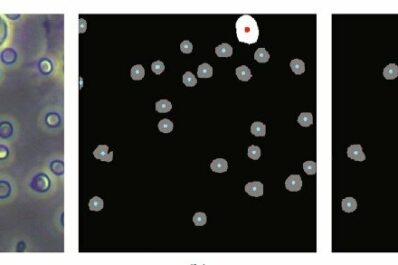

The use of machine learning to perform blood cell counts for diagnosis of disease instead of expensive and often less...